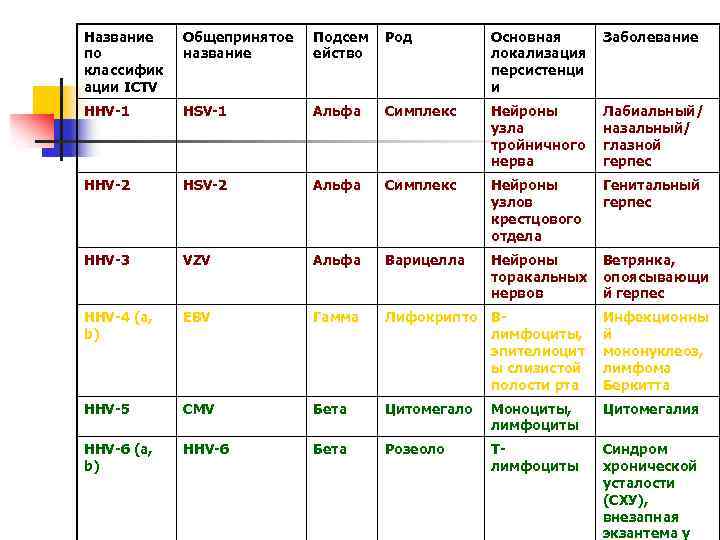

Название по классифик ации ICTV Общепринятое название Подсем ейство Род Основная локализация персистенци и Заболевание HHV-1 HSV-1 Альфа Симплекс Нейроны узла тройничного нерва Лабиальный/ назальный/ глазной герпес HHV-2 HSV-2 Альфа Симплекс Нейроны узлов крестцового отдела Генитальный герпес HHV-3 VZV Альфа Варицелла Нейроны торакальных нервов Ветрянка, опоясывающи й герпес HHV-4 (a, b) EBV Гамма Лифокрипто Влимфоциты, эпителиоцит ы слизистой полости рта Инфекционны й мононуклеоз, лимфома Беркитта HHV-5 CMV Бета Цитомегало Моноциты, лимфоциты Цитомегалия HHV-6 (a, b) HHV-6 Бета Розеоло Тлимфоциты Синдром хронической усталости (СХУ), внезапная экзантема у

Название по классифик ации ICTV Общепринятое название Подсем ейство Род Основная локализация персистенци и Заболевание HHV-1 HSV-1 Альфа Симплекс Нейроны узла тройничного нерва Лабиальный/ назальный/ глазной герпес HHV-2 HSV-2 Альфа Симплекс Нейроны узлов крестцового отдела Генитальный герпес HHV-3 VZV Альфа Варицелла Нейроны торакальных нервов Ветрянка, опоясывающи й герпес HHV-4 (a, b) EBV Гамма Лифокрипто Влимфоциты, эпителиоцит ы слизистой полости рта Инфекционны й мононуклеоз, лимфома Беркитта HHV-5 CMV Бета Цитомегало Моноциты, лимфоциты Цитомегалия HHV-6 (a, b) HHV-6 Бета Розеоло Тлимфоциты Синдром хронической усталости (СХУ), внезапная экзантема у